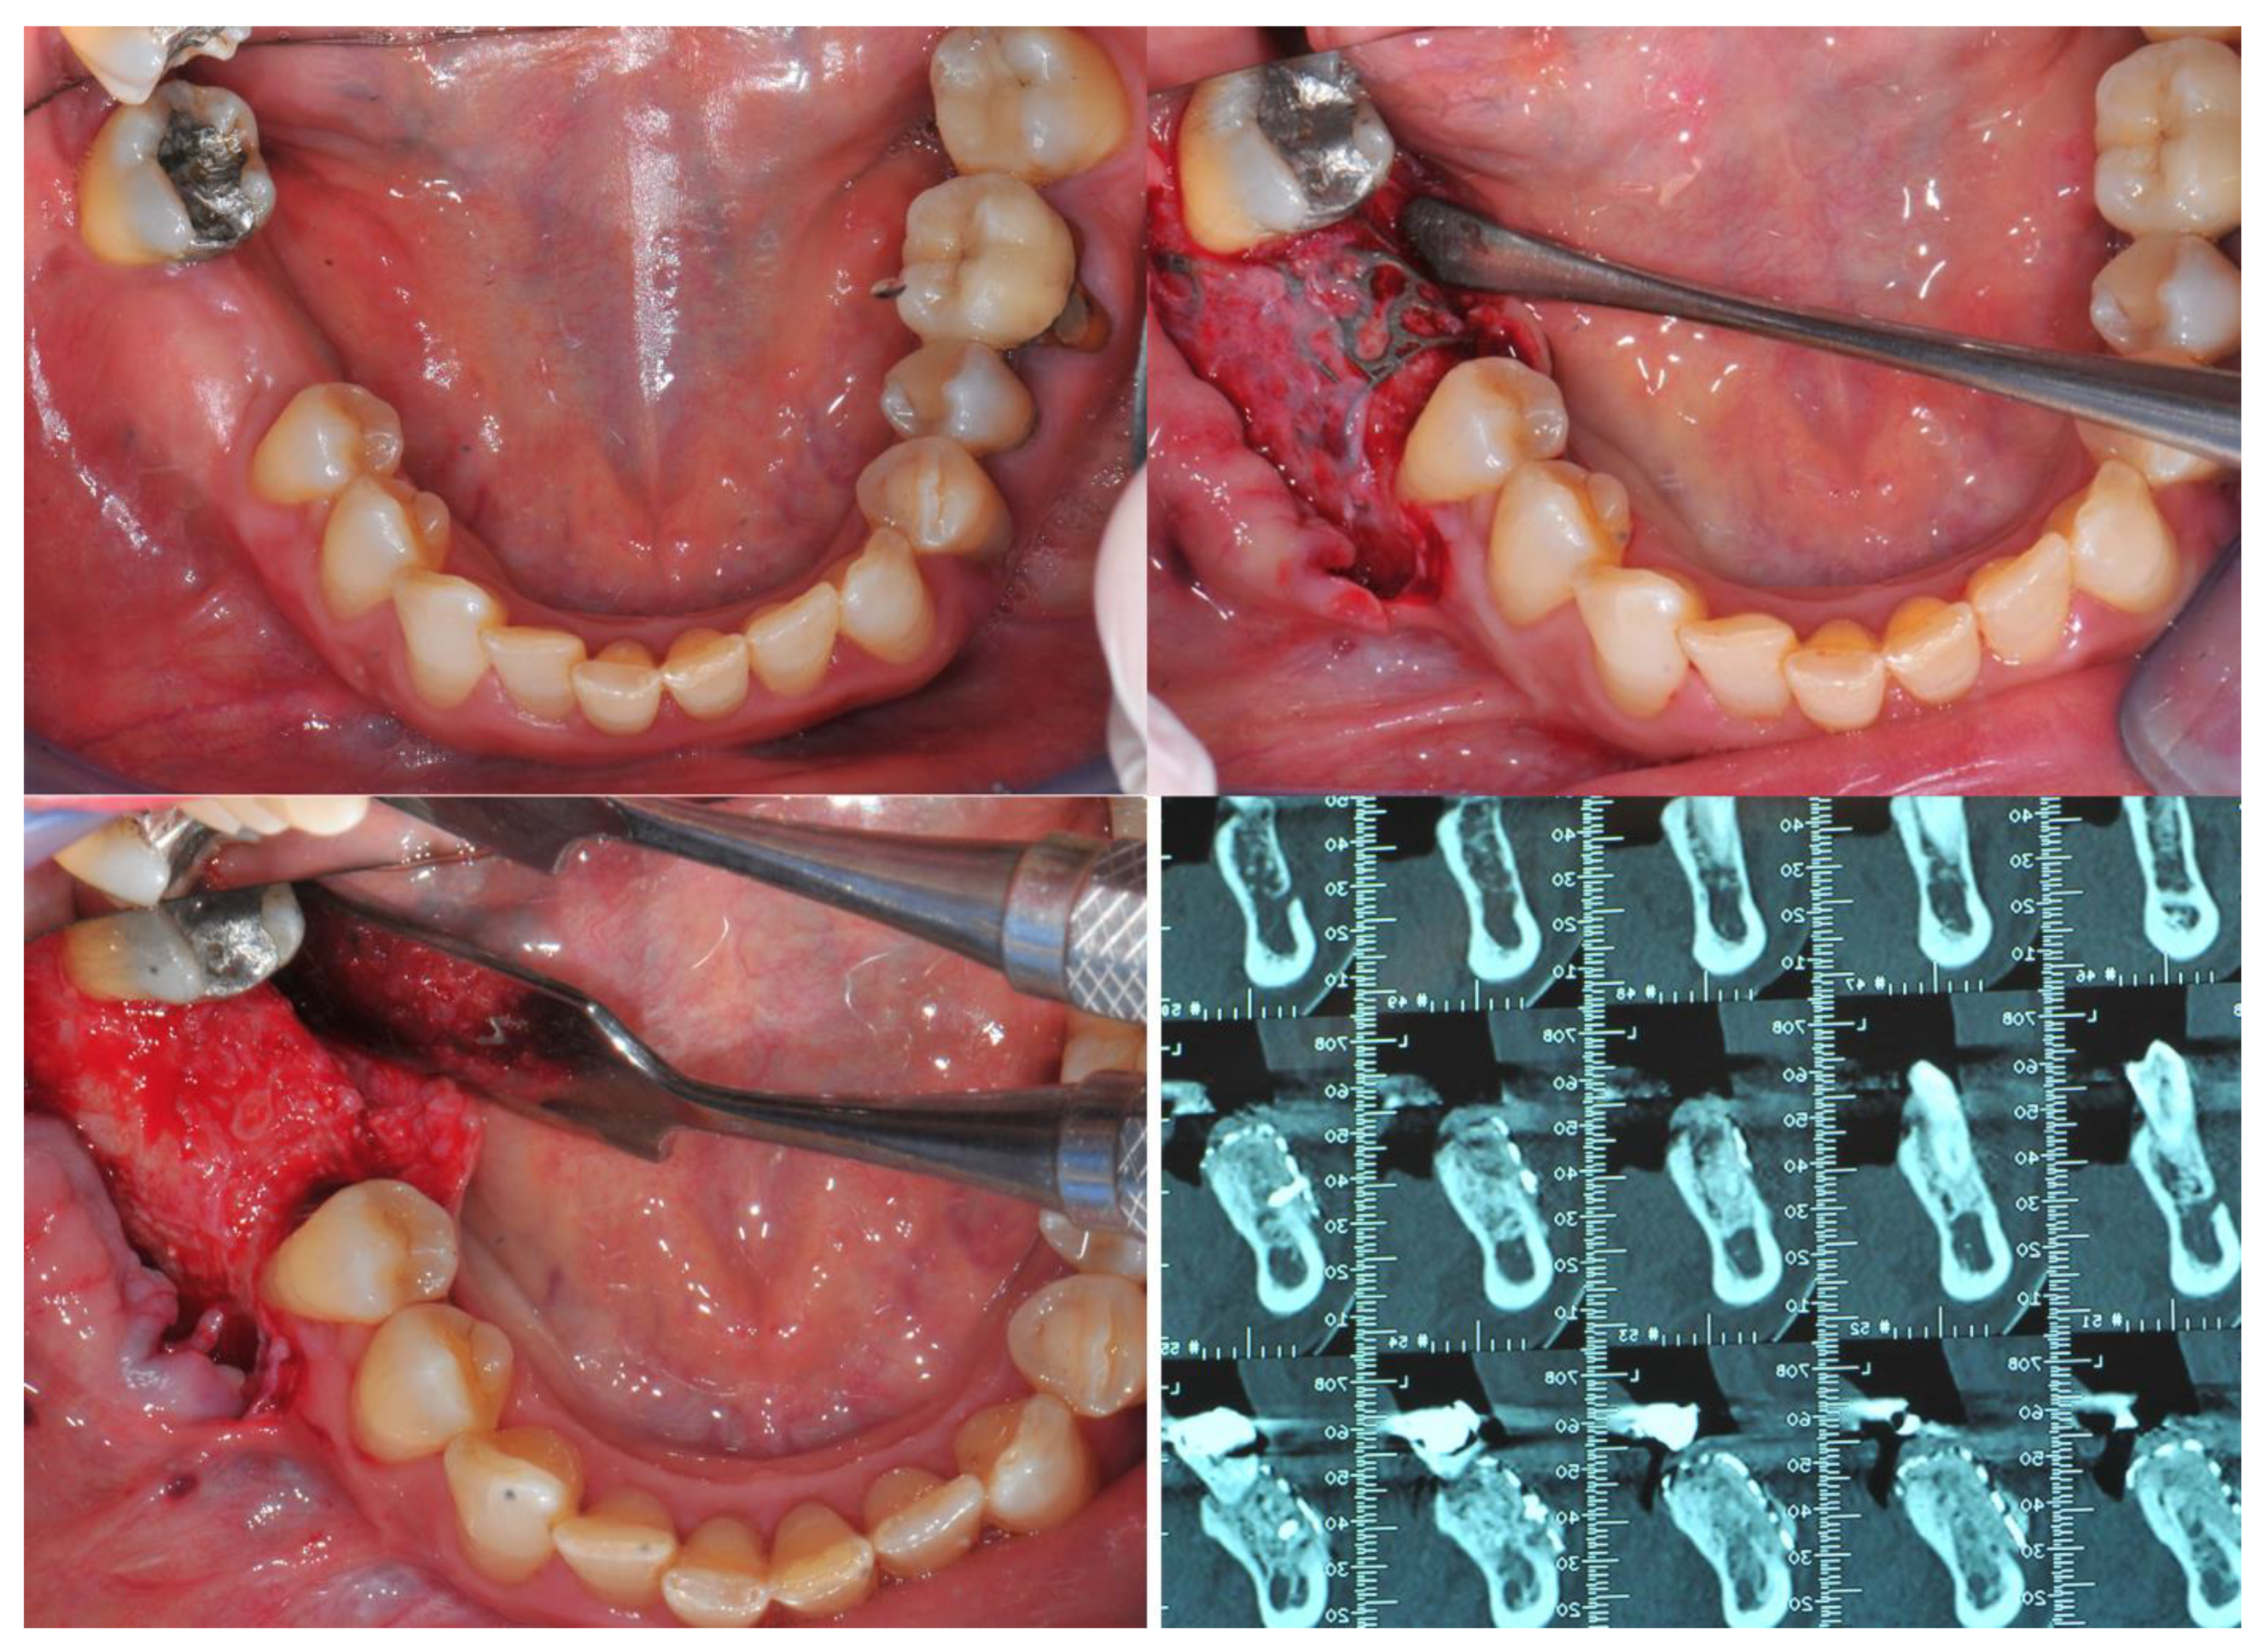

Figure 2.

CBR involving upper jaws. Top line, from left to right: initial clinical situation, flap design, bone refreshing. Bottom line from left to right: CBR in place, covering of it with a resorbable membrane, implanting of insertion after grid removal and clinical evaluation of the bone quality obtained.